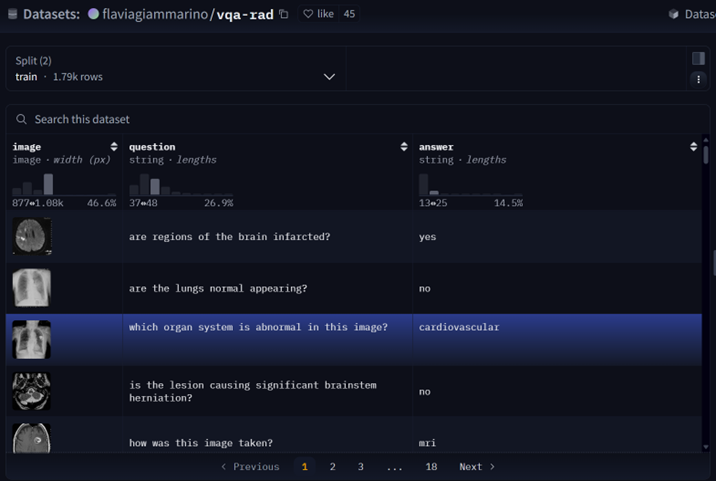

VQA-RAD 是一个关于放射影像的问题-答案对数据集(https://huggingface.co/datasets/flaviagiammarino/vqa-rad )。

📌数据集用途

- 训练和测试医学影像VQA(视觉问答)系统

- 支持开放式问题(如“病灶位置?”)和二元问题(如“是否存在肿瘤?”)

📌数据来源

- 基于MedPix(开放医学影像数据库)

- 由临床医生手动标注,确保专业性

📌核心优势

- 首个专注放射影像的VQA数据集

- 结构清晰,覆盖临床常见问题类型

No.2 数据处理

1.数据获取

2.处理前

{"image": <PIL.JpegImagePlugin.JpegImageFile image mode=RGB size=566x555>,"question": 'are regions of the brain infarcted?',"answer": 'yes'

}

3.处理后(OpenAI格式)

[{"messages": [{"content": "<image>are regions of the brain infarcted?","role": "user"},{"content": "yes","role": "assistant"}],"images": [path/to/train_image_0.jpg"]},